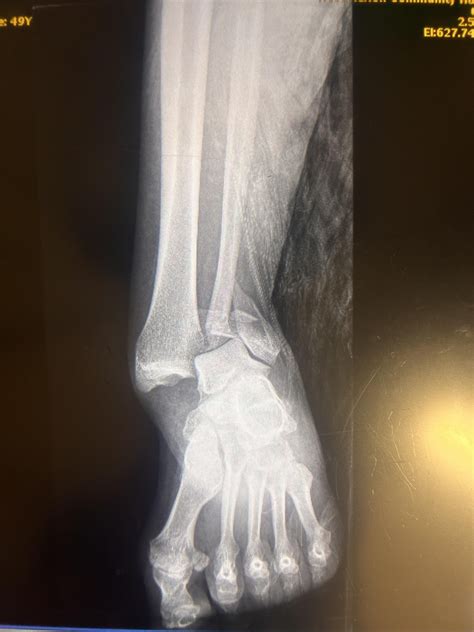

• Hard Callus Formation: Over several weeks, the cartilage is replaced by hard bone, known as a bony callus. This is a visible union on X-rays, indicating the bone is regaining strength.